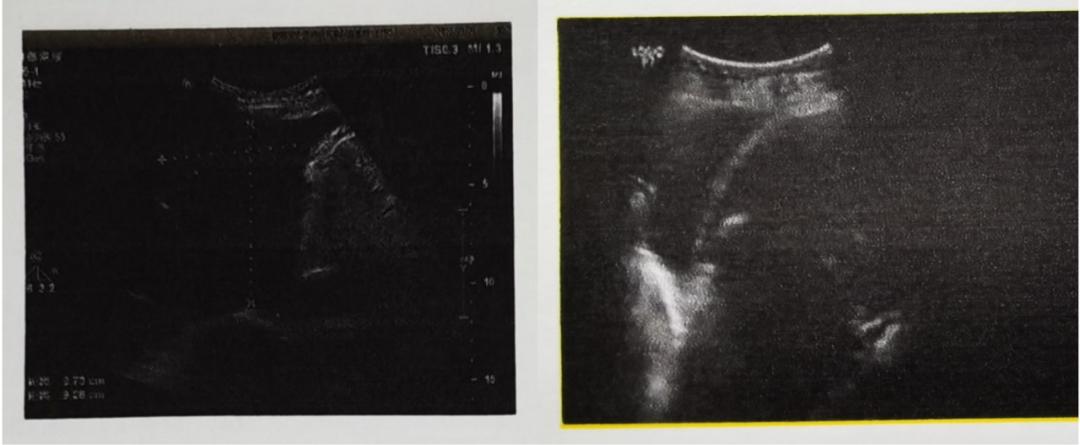

3月28日彩超报告单(左:提示左侧胸腔大量积液)和4月3日彩超报告单(右:提示左侧胸腔中量积液)

4月8日彩超报告单(左:提示左侧胸腔少量积液)和4月15日彩超报告单(右:提示左侧胸腔极少量积液)